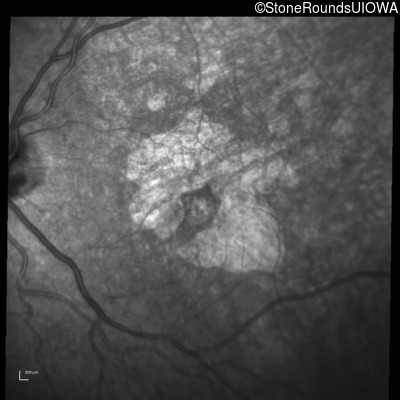

Infrared Fundus Photograph - Right - 20/32 +2

Exemplar